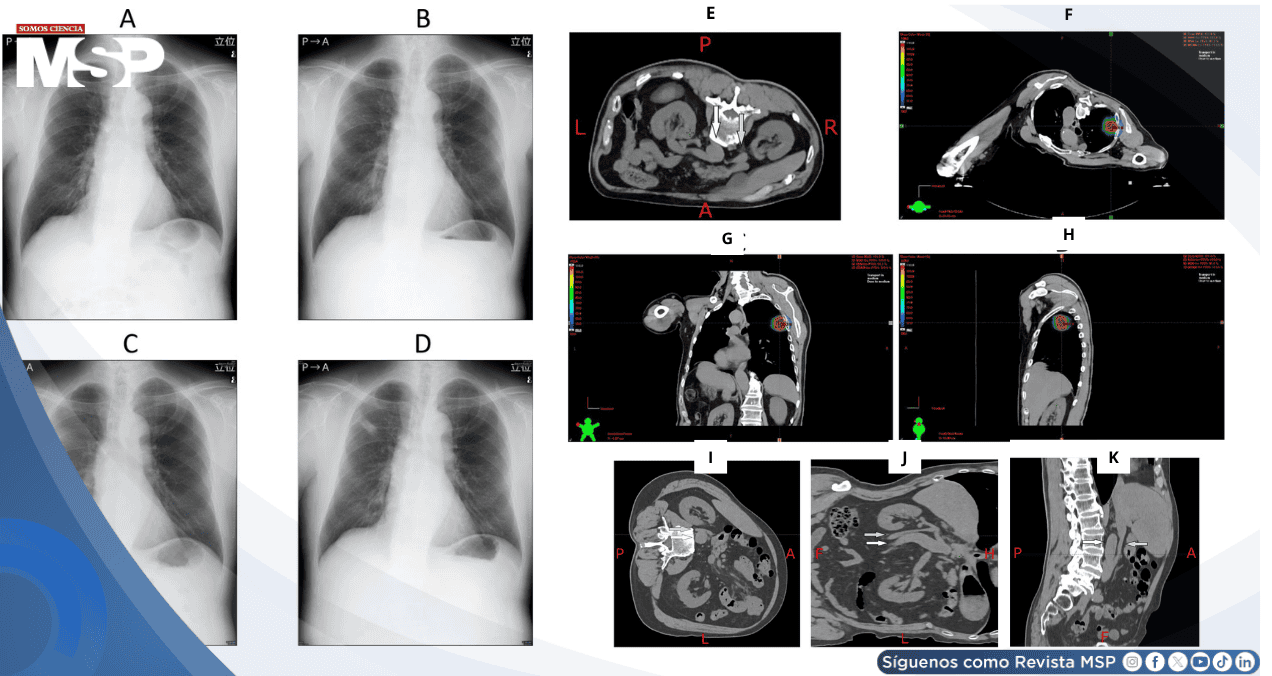

Las imágenes mostraron una vena cava inferior comprimida entre el riñón derecho y una aorta abdominal tortuosa, sin evidencia de masas o tumores retroperitoneales. Esta disposición anatómica explicaba el pinzamiento dinámico de la VCI al adoptar ciertas posiciones, reduciendo el retorno venoso y desencadenando síntomas de hipotensión.

Ante la imposibilidad de realizar el tratamiento en posición supina, el equipo de radioterapia modificó la técnica de SBRT, eligiendo la posición prona con inclinación lateral derecha, que evitaba la compresión.

El paciente fue tratado con 56 Gy en cuatro fracciones, utilizando terapia de arco modulado por volumen. El monitoreo intraoperatorio no mostró recurrencia de los síntomas, y el tratamiento fue completado con éxito.